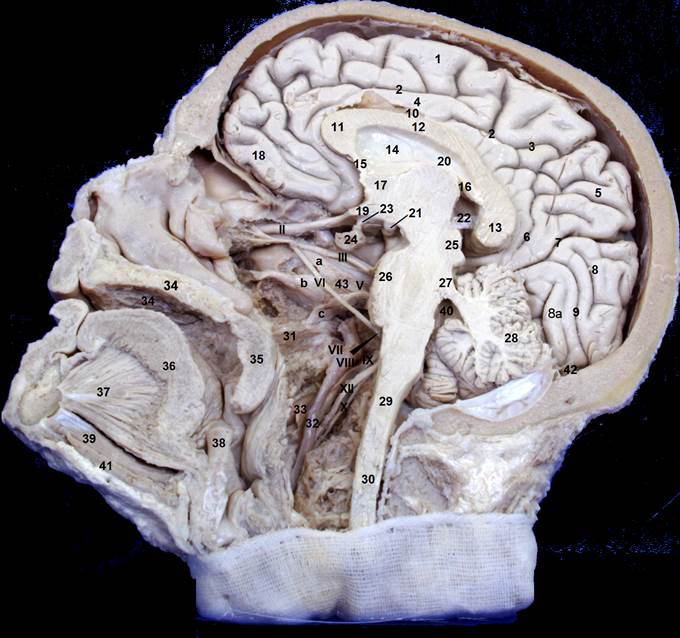

Рис. Cагиттал.распил головыIMG_3806_red